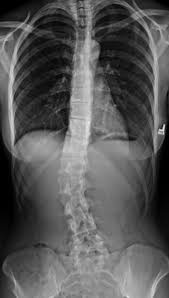

척추 측만증은 척추가 정면에서 봤을 때 일직선이 아닌 옆으로 휘어지면서 회전까지 동반되는 상태를 말합니다. 단순히 허리가 굽거나 등이 구부정한 자세 문제와는 다르게, 척추 자체의 구조적 변형이 포함된 질환입니다.

척추 측만증 증상은 통증보다 몸의 비대칭으로 먼저 나타나는 경우가 많습니다. 다음과 같은 변화가 느껴진다면 한 번쯤 체크해볼 필요가 있습니다.

- 어깨 높이가 서로 다름

- 한쪽 날개뼈가 더 튀어나와 보임

- 허리 라인이 좌우 비대칭